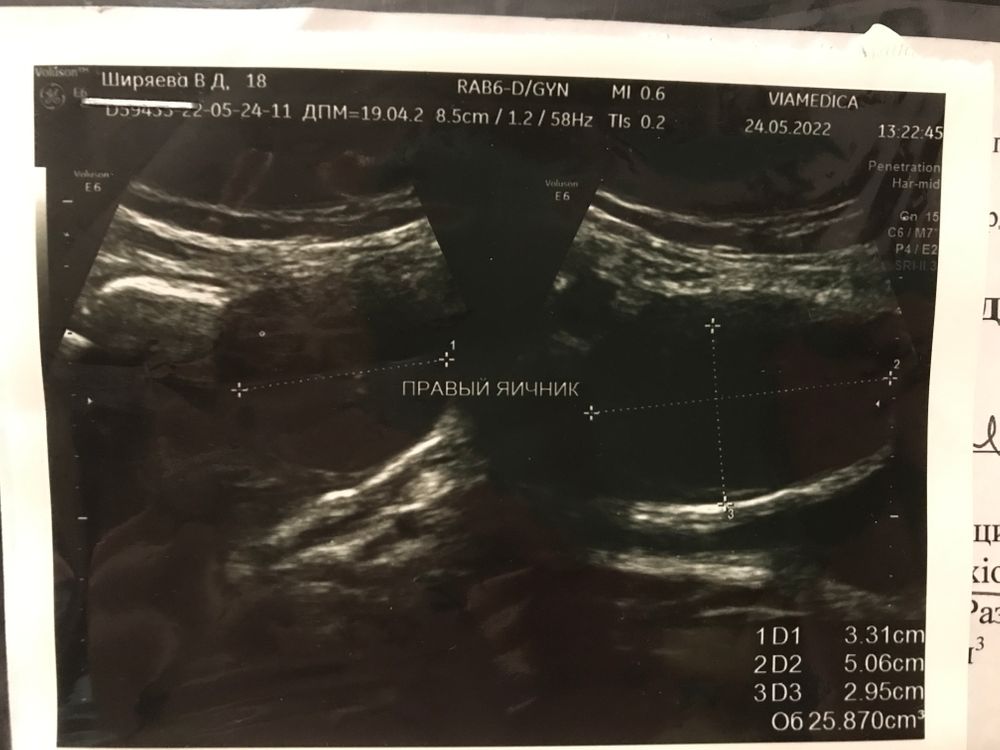

Киста жт с кровоизлиянием. В принципе ничего страшного, главное чтобы не лопнула

Ангелина, тоже вот очень переживаю за это, порой особенно по утрам ужасно бок болит аж гнёт разогнуться не могу, да так болит что аж кровь из носа идёт, а в течении дня после такой боли живот ноет, уже по скорой ездить устала, говорят хорошо все😒